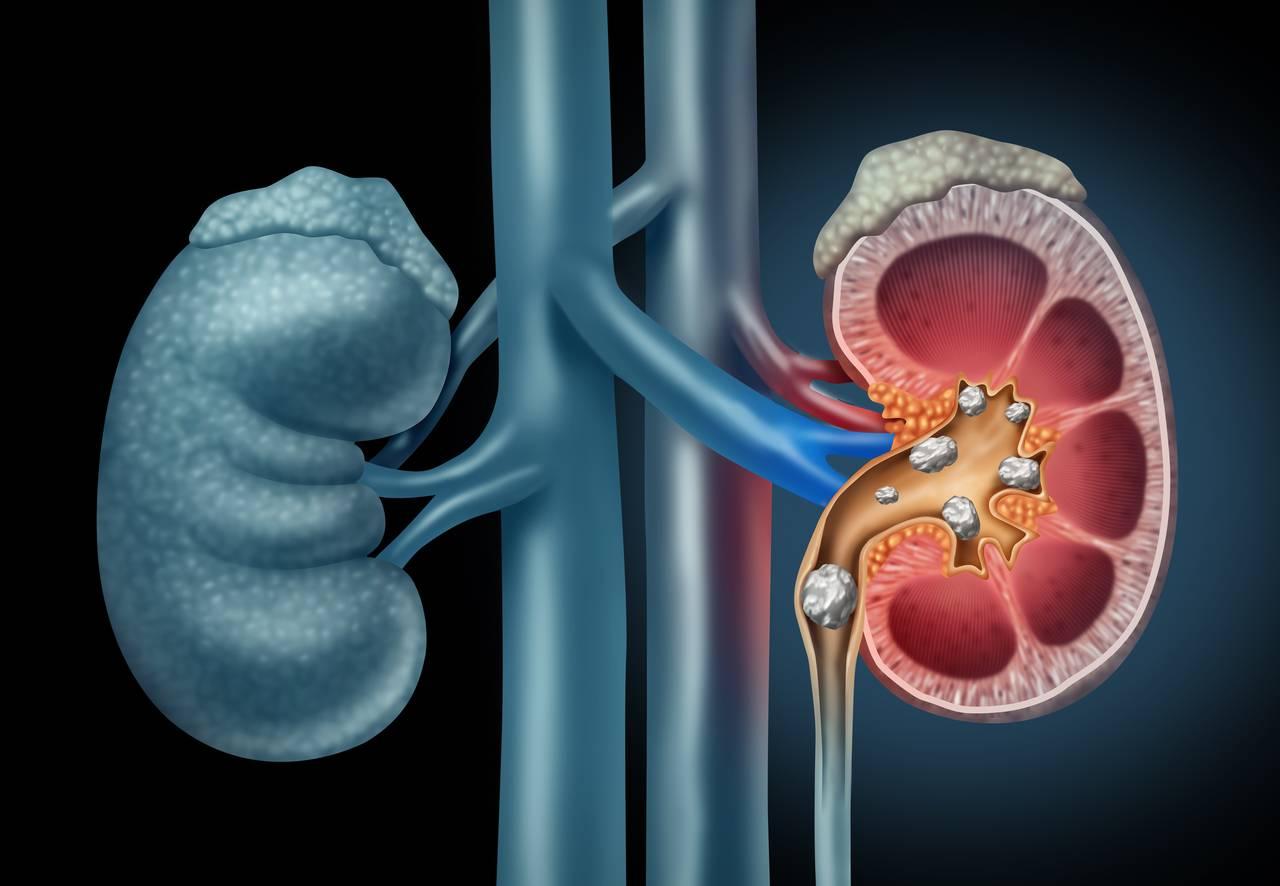

Calculii renali sunt depozite solide formate din minerale și săruri care se pot dezvolta în sistemul urinar. Ele rezultă din cristalizarea unor substanțe prezente în urină și pot varia ca mărime, structură și compoziție, de la granule foarte mici până la mase care pot obstrucționa fluxul urinar. Tipurile frecvente includ calculi pe bază de calciu, acid uric, struvit sau cistin, fiecare având mecanisme de formare și factori predispozanți ușor diferiți.

Formarea calculilor poate fi influențată de factori precum volumul redus de urină, modificări ale compoziției urinare sau anumite condiții metabolice; acești factori pot contribui la creșterea concentrației unor substanțe care favorizează cristalizarea. În multe cazuri, prezența unui calcul poate determina durere sau alte simptome care pot necesita evaluare și management medical adecvat, iar strategiile preventive sau terapeutice sunt adaptate în funcție de tipul și severitatea problemei.

Formarea calculilor apare în general când urina devine supersaturată cu substanțe care cristalizează; condiții care modifică compoziția urinei pot favoriza acest proces. Tipuri frecvente includ calculi pe bază de calciu (de obicei oxalat sau fosfat), acid uric, struvit sau cistină, iar fiecare tip are mecanisme metabolice ușor diferite care pot contribui la formare. Anumite tulburări metabolice, precum și unele medicamente sau intervenții chirurgicale, pot influența echilibrul electroliților sau pH-ul urinei și astfel pot crește predispoziția la pietre.

Factorii care pot crește riscul includ în mod frecvent consumul insuficient de lichide, dietă bogată în sodiu sau în proteine animale, aport crescut de oxalați alimentari și condiții metabolice asociate cu excesul de calciu sau acid uric în urină; obezitatea, istoricul familial și anumite anomalii anatomice ale tractului urinar pot, de asemenea, să joace un rol. Infecțiile urinare recurente pot favoriza apariția calculilor de tip struvit. Pentru resurse suplimentare privind prevenția și cauzele specifice, consultați informații despre calculi renali.